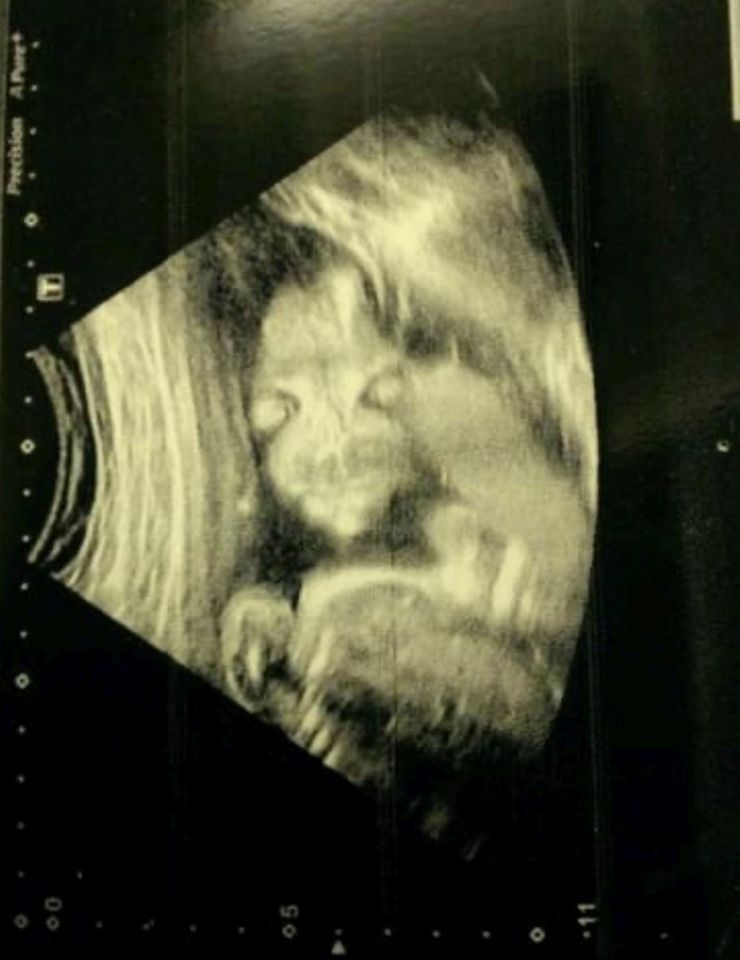

據悉,這是 Jade 7歲長女Lydia的超聲波照。Jade記得當時懷孕20週的她滿心期待前往醫院進行超聲波檢查,已經準備好和家人及朋友分享胎兒的超聲波照。結果,她卻赫然被照片上極其詭異的畫面嚇壞了。照片中的胎兒就像有長長的爪子,還有兩個大大的眼睛,正盯著大家看, Jade坦言當下以為看見了「惡魔」,不知如何是好,還擔心她是異形兒。

不過醫生見狀卻笑著聲稱一切都沒問題,要她別擔心。隨即醫生解釋,這是因為胎兒身體朝外,才會被拍到如此詭異的畫面。 Jade懷著忐忑的心回了家,試過不同方法試圖讓胎兒轉身,然而那之後她也沒再照過超聲波了。最後, Jade通過剖腹產生下健康的女兒,她第一時間就是檢查孩子的樣貌,確認一切正常才讓她鬆了口氣。